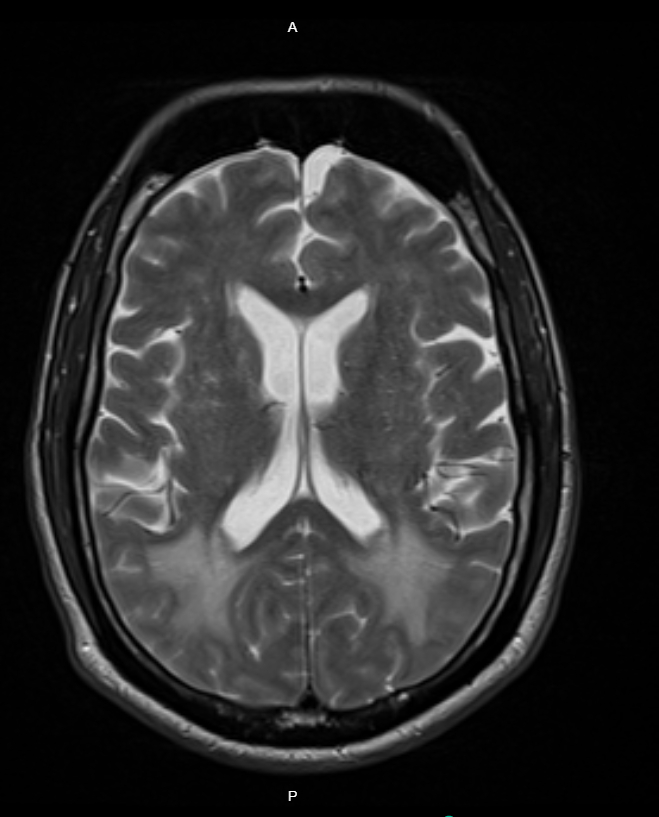

A Head CT showed diffuse white matter hypoattenuation concerning for vasogenic edema or posterior reversible encephalopathy syndrome (PRES). He received 25 mg IV hydralazine and started an IV nicardipine drip, lowering his SBP to 200 mmHg within the first hour and admitted to MICU.

After 48 hours, head MRI showed new punctate infarcts consistent with lacunar strokes. MRI Angiography was unremarkable. The patient developed altered mental status, hypotension, and respiratory failure requiring intubation. Repeat CT head showed new right frontal hypoattenuation suggestive of infarction. Antihypertensives were held, and bumetanide drip started for suspected pulmonary edema. After 48 hours, continuous renal replacement therapy was initiated due to worsening renal function. He was extubated on day 5. On day 9, he developed expressive aphasia with preserved strength. He was stabilized and discharged with multidisciplinary follow-up.